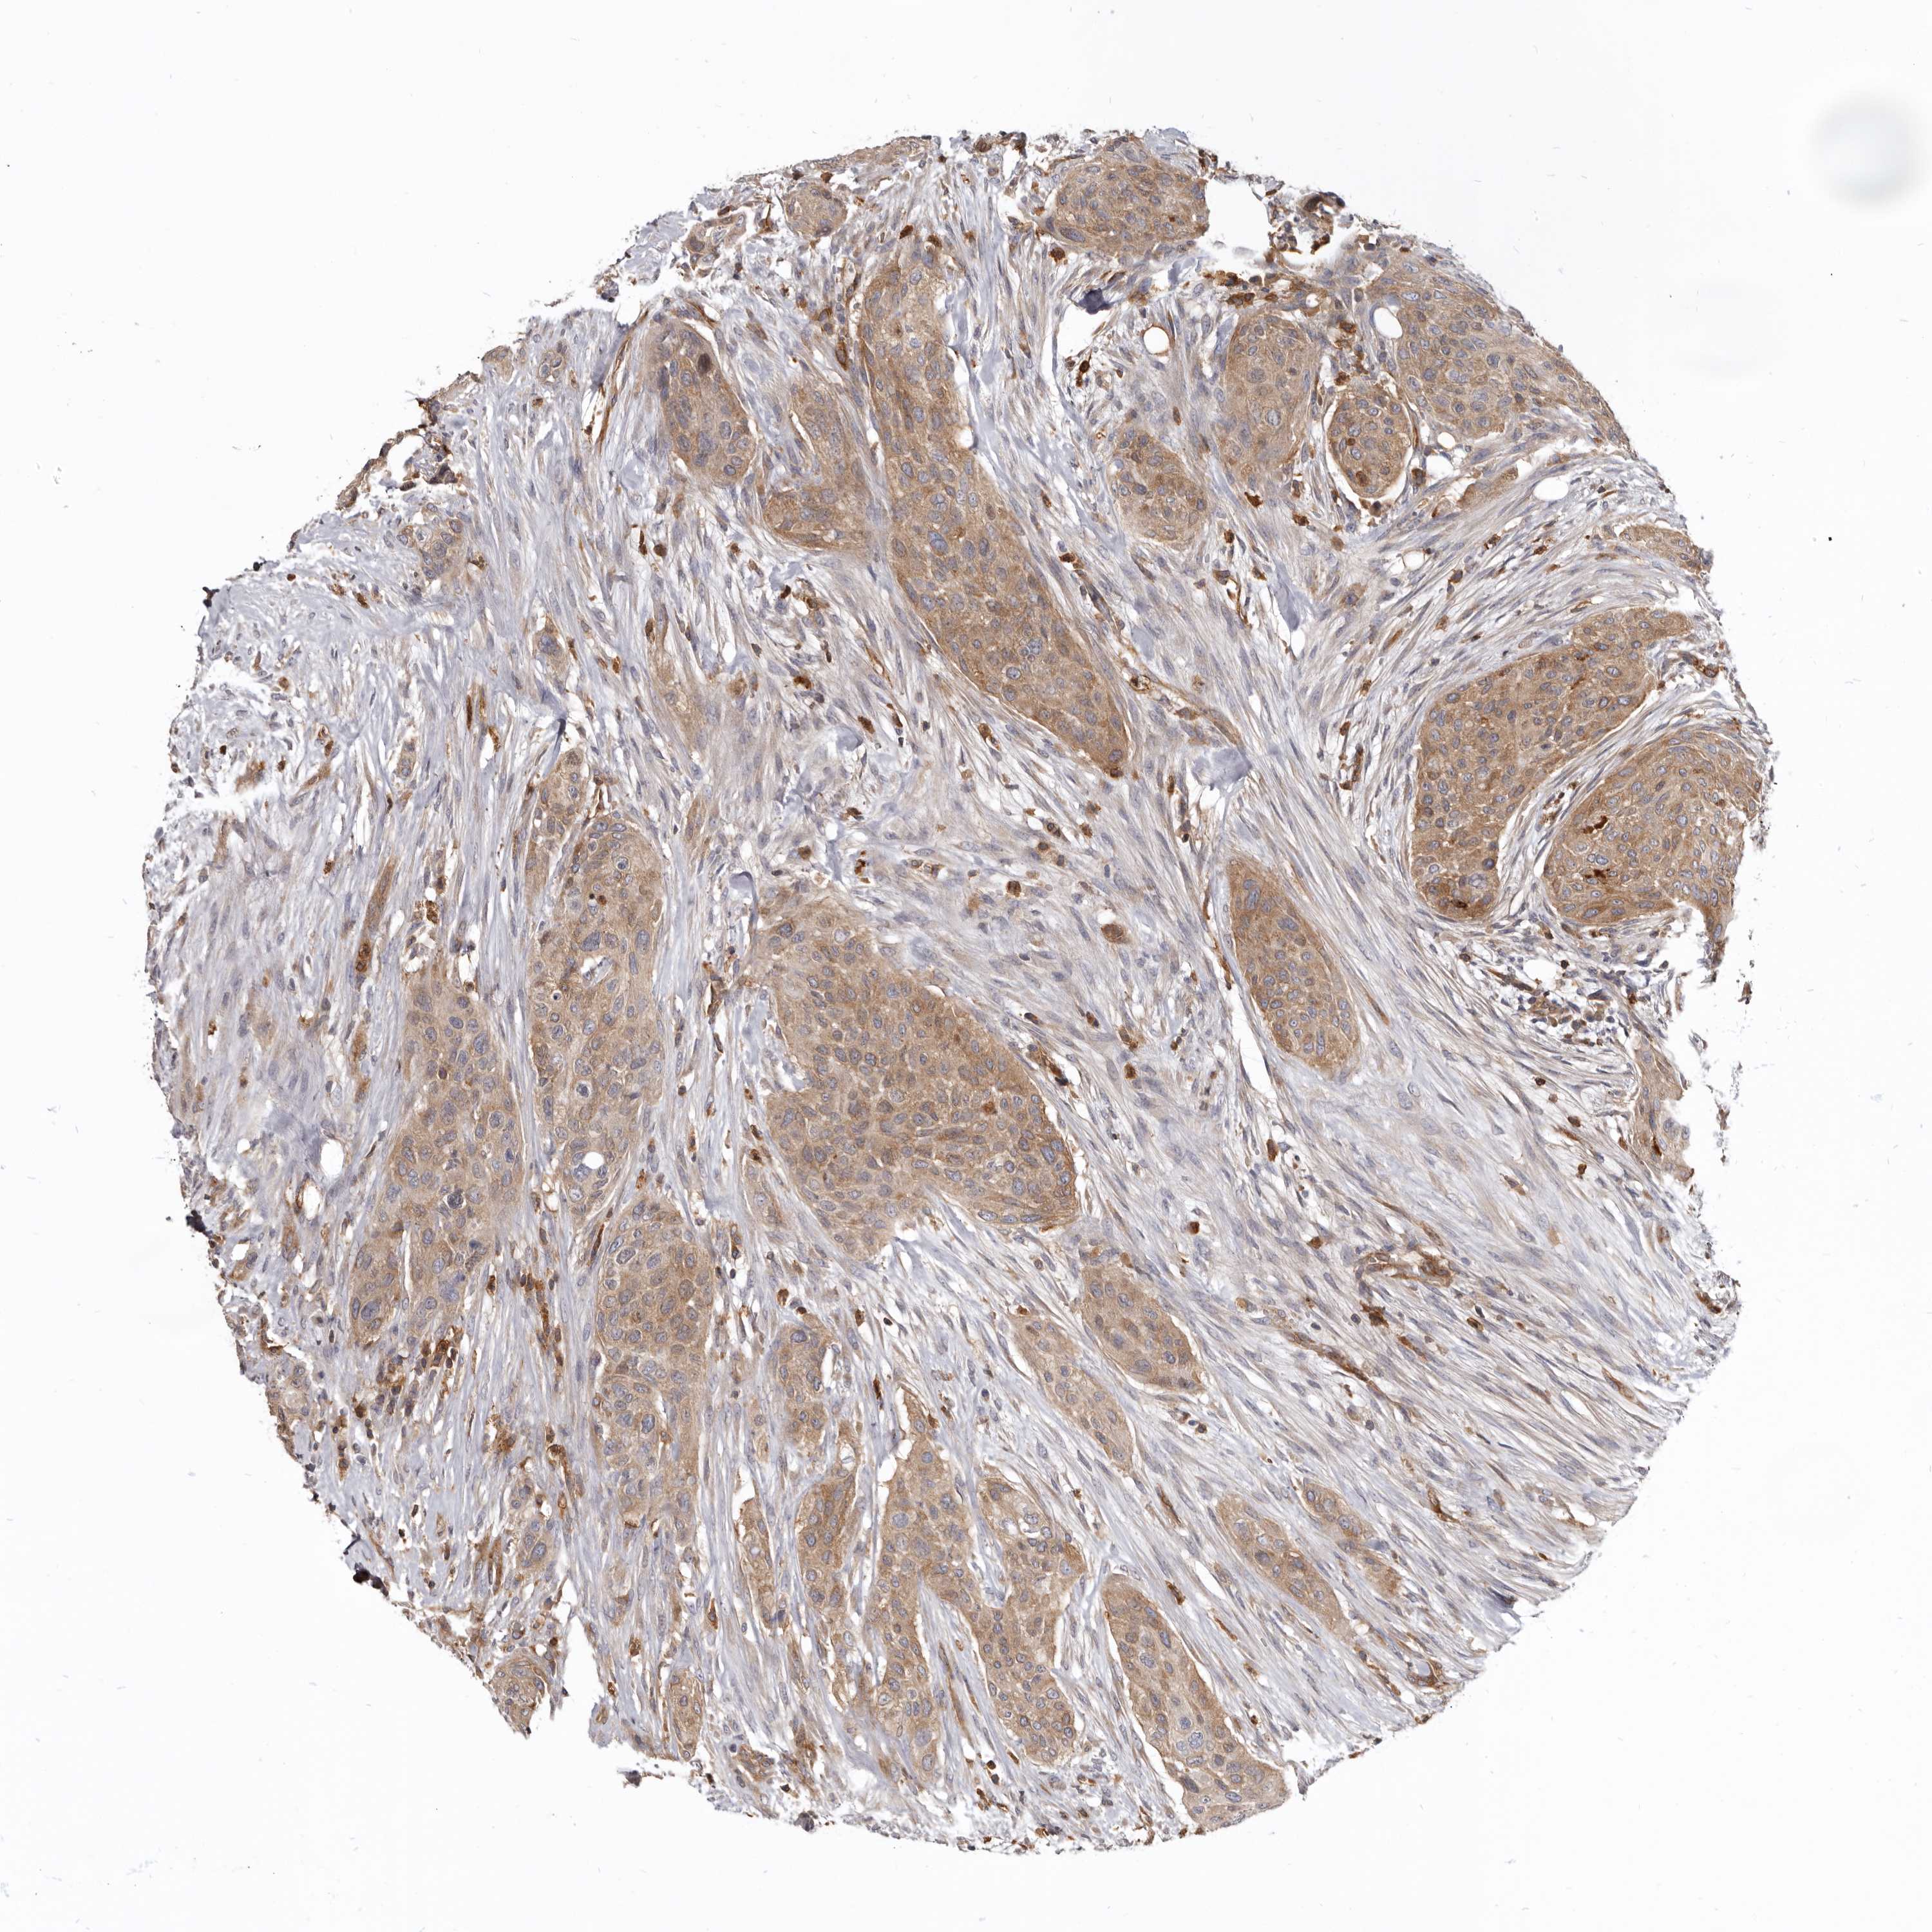

UROTHELIAL CANCER - Protein expressioni

A mouse-over function shows sample information and annotation data. Click on an image to view it in a full screen mode. Samples can be filtered based on level of antibody staining by selecting one or several of the following categories: high, medium, low and not detected. The assay and annotation is described here.

Antibody stainingi

Antibody staining in the annotated cell types in the current human tissue is reported as not detected, low, medium, or high, based on conventional immunohistochemistry profiling in selected tissues. This score is based on the combination of the staining intensity and fraction of stained cells.

Each image is clickable and will lead to virtual microscopy that enables deeper exploration of all samples and also displays staining intensity scores, fraction scores and subcellular localization as well as patient and tissue information for each sample.

Antibody HPA027956

Antibody CAB004350

Staining

High

Medium

Low

Not detected

Intensity

Strong

Moderate

Weak

Negative

Quantity

>75%

75%-25%

<25%

None

Location

Nuclear

Cytoplasmic/membranous

Cytoplasmic/membranous,nuclear

Urothelial carcinoma, Low grade

Urothelial carcinoma, High grade